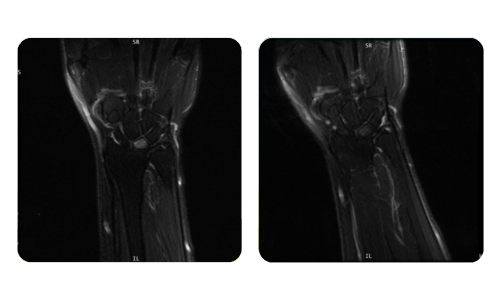

Progresul pacienților noștri, măsurat înainte și după terapia hiperbară, reflectă eficiența și impactul pozitiv al tratamentului. Descoperă rezultate documentate ale terapiei hiperbare la clinica Hyperbarium Oradea, bazate pe evaluări clinice și date obiective care evidențiază îmbunătățiri semnificative în diverse afecțiuni.